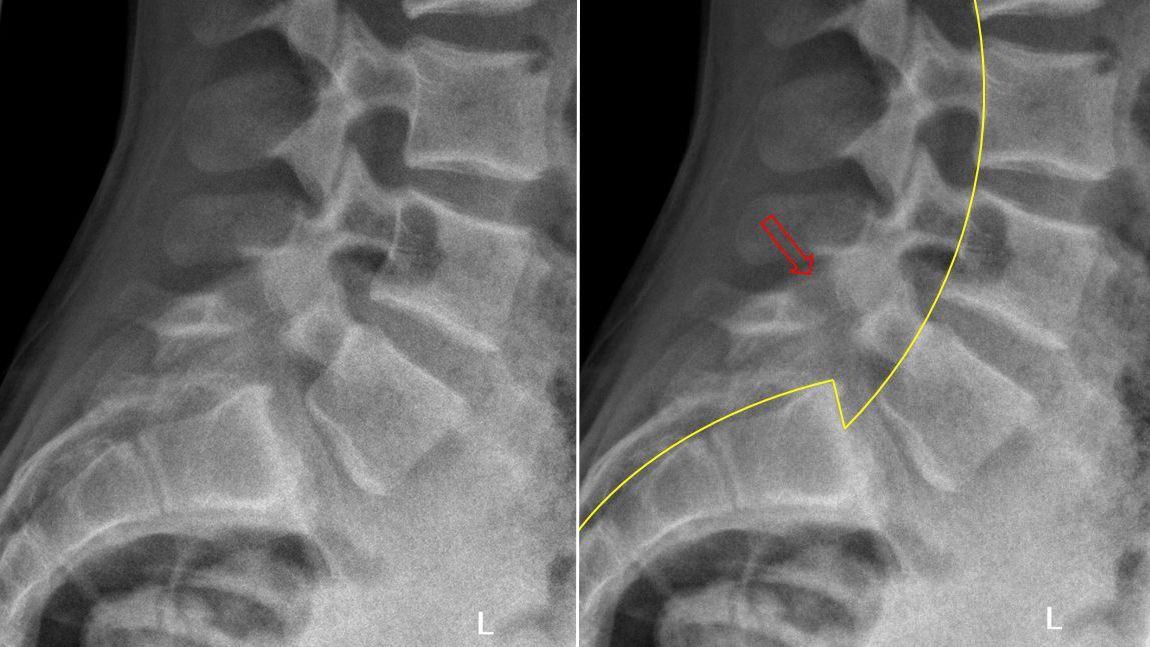

Een spondylolyse is een onderbreking in de wervelboog van een lendenwervel. Deze kan acuut optreden na intense beoefening van bepaalde sporten maar kan ook toevallig vastgesteld worden en dus reeds langer bestaande zijn. Wanneer een spondylolyse zich aan weerszijden van eenzelfde wervelboog voordoet, kan dit (vooral tijdens de groeispurt) tot een afschuiving van het ene wervellichaam ten opzichte van het andere leiden (=spondylolisthesis).

Opmerking : Soms zien we ook een afschuiving van de wervels zonder dat er een werkelijke onderbreking in de wervelboog aanwezig is. Dit wordt dan een degeneratieve spondylolisthese genoemd omdat deze veroorzaakt wordt door slijtage.

Bij acuut optreden van lage rugpijn en vermoeden van spondylolyse is botscan het ideale onderzoek. Een staande klassieke radiografie kan ons een beeld geven van de werkelijke graad van afschuiven. In liggende positie zien we immers dat de wervel terug op zijn plaats komt te staan. Bij aanwezigheid van beenpijn is verder onderzoek dmv NMR aangewezen.